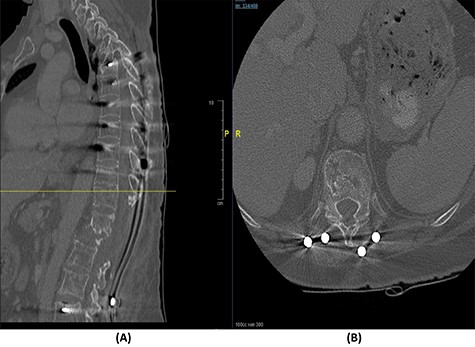

Fourteen months later, the patient presented to the ED complaining of generalized body pain associated with malaise. The neurological examination was unremarkable. An MRI of the lumbar spine showed recurrence of the lesion with loosening and pullout of the implant, kyphosis and dislocation, with cord compression and collection (Fig. 2). Computed tomography (CT) scan showed a burst fracture of the L1 vertebra with loose screws (Fig. 3). CRP was 21 mg/l, ESR was 115 mm/h and procalcitonin was 0.051 ng/ml. The decision was made to do a CT-guided biopsy from the left paraspinal mass of T12–L1. The tissue biopsy was subjected to TB-polymerase chain reaction testing and acid-fast bacillus culture; both results were positive for M. tuberculosis. The patient was diagnosed with TB spondylitis and was started on the full anti-TB four-drug regimen.

(A) T2-weighted sagittal spine MRI demonstrating changes at the thoracolumbar spine with previous decompression for pathological fracture of L1 vertebra. There is interval progression of the disease with a soft tissue mass at the previous site extending to the prevertebral and epidural spaces, compressing the neural element. (B) T2-weighted axial spine MRI of the corresponding level of L1 vertebral body.